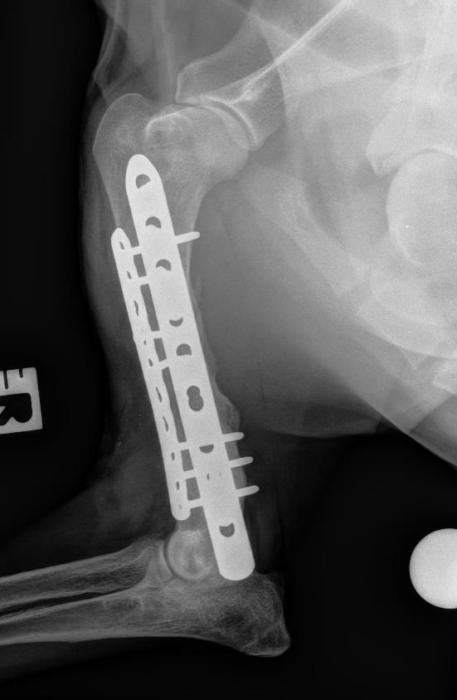

We work to translate therapeutic solutions that address clinical needs in bone regeneration. Our research relies in the use of acellular and cell based complementary strategies to guide stem cell differentiation into osteogenic precursors. Our work has progressed to preclinical models of non-union bone defects and we have planned to start clinical phases with a cell therapy in late 2020. Our core technologies for bone regeneration aim to: